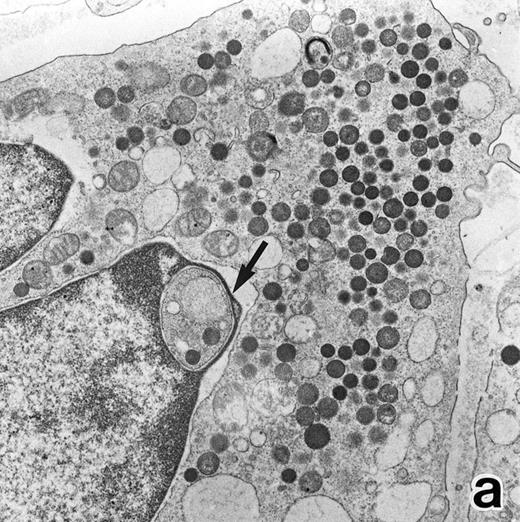

(a) A PMN that emerged in the APL cell culture of patient no. 3 in the presence of ATRA for 1 week. From the lobulated nuclear configurations and condensed heterochromatin, this cell looks like a PMN. However, the cytoplasm contains many MPO-positive primary granules but no secondary granules. (MPO-stained section, original magnification × 14,900.) (b) Higher magnification of a portion of the cell in (a), showing that the cytoplasmic granules are all MPO-positive. (MPO-stained section, original magnification × 30,100.)